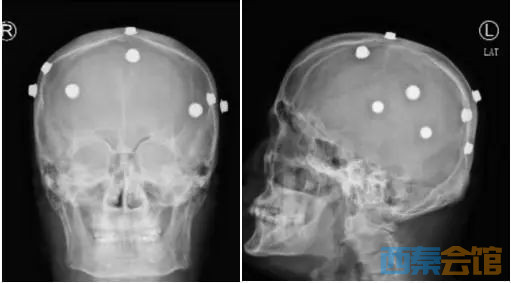

头颅X片显示李大哥的头皮布满了“金属异物”

据了解,早在2002年,安徽池州的李大哥第一次出现了无明显诱因下意识丧失伴四肢抽搐的症状,但不一会儿,症状就好转了,李大哥便没怎么在意,也没有去医院进行治疗。但随着时间的推移,李大哥发病的次数越来越频繁,家人也十分着急,四处打听,求医问药。

一次偶然的机会,在远房亲戚的介绍下,李大哥去了外地就诊。“医生”在李大哥头皮下植入了8枚“纽扣电池”样金属片,并称可借助头皮“避雷针”的作用,将导致癫痫发作的异常脑电引走,从而将癫痫“化为无形”。